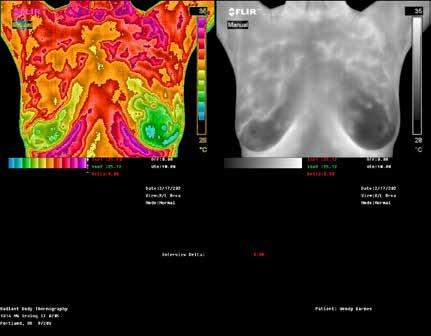

TOP: Thermographic pattern of physician-confirmed estrogen dominance, which the client addresses. BOTTOM: Images show success in removing the estrogen dominance pattern & client also downgrades her abnormal right breast! Estrogen dominance has a heat signature visible with QUALITY Thermography.